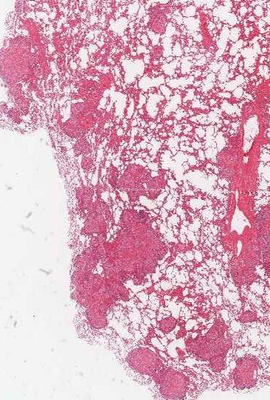

Longembolie met longinfarct. Welke structuur is aangegeven?

Answer

• arteria pulmonalis